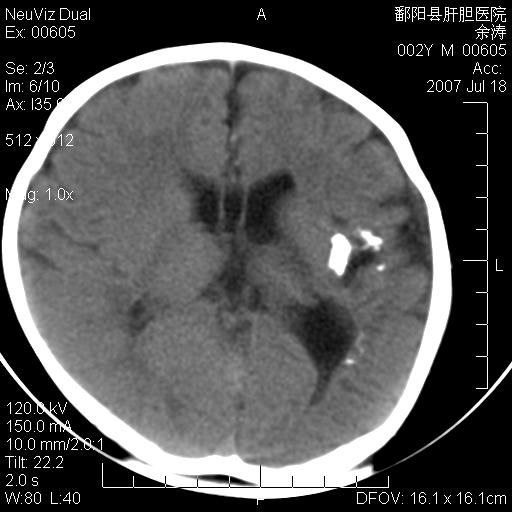

男性 2岁:平时智力障碍。外伤后行颅脑平扫。

左颞叶“萎缩”,可见不规则高密度影,并左侧室扩大,呈负占位效应...支持考虑先天发育异常(血管发育畸形)可能性大,建议结合进一步检查了解。

左颞叶“萎缩”其内可见不规则点条状高密度影,并左侧室扩大,考虑颅面血管瘤病

左侧颞顶叶钙化灶,其内有小片状低密度影 边缘清晰。与之相邻的脑沟增宽增深 ,左侧侧脑室体部牵拉扩大。考虑左颞顶软化灶并局限性脑萎缩。透明隔间腔。

该病人应该还有胼胝体发育不全